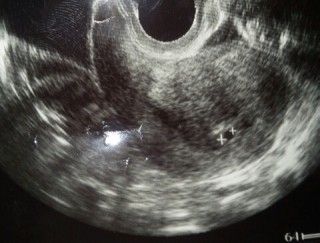

昨日病院にいってきました! まだ4.7mmしかないけど、 ちゃんとお腹にいてくれました♥︎ 再来週、また病院に行くのが楽しみです。